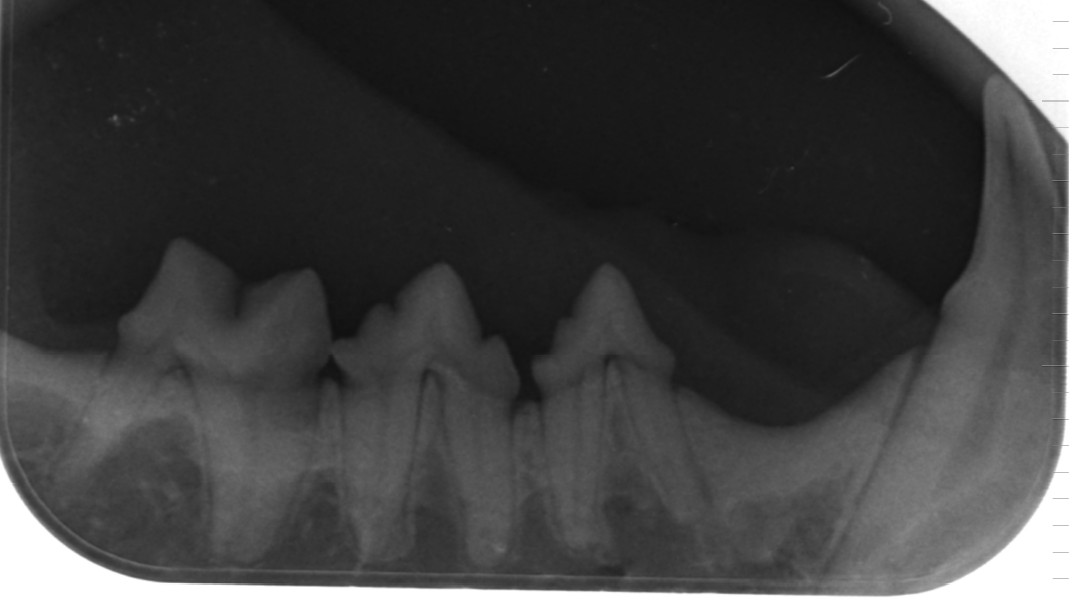

Seit 2001 sind wir für alle Zweifelsfälle auch mit einer digitalen Röntgeneinheit ausgestattet, die besonders feine Aufnahmen mit hoher Transparenz ermöglicht. Diese Röntgenbilder sind in Ihrer Aussagefähigkeit deutlich besser als normale Röntgenaufnahmen und ersparen damit häufig die Anfertigung einer Computertomographie. Herkömmliche Röntgenaufnahmen können bei uns ebenfalls durch Digitalisierung in die Datenverarbeitung genommen werden. In dieser Form sind sie als E-Mail versendbar. Seit 2019 haben wir auch eine digitale Zahnröntgeneinheit. Das erleichtert und beschleunigt die Zusammenarbeit mit beratenden Kollegen sowie die Informationsübermittlung bei Überweisungen auch über weite Distanzen.

Zahnsanierung / Dentalröntgen

Digitales Zahnröntgen.